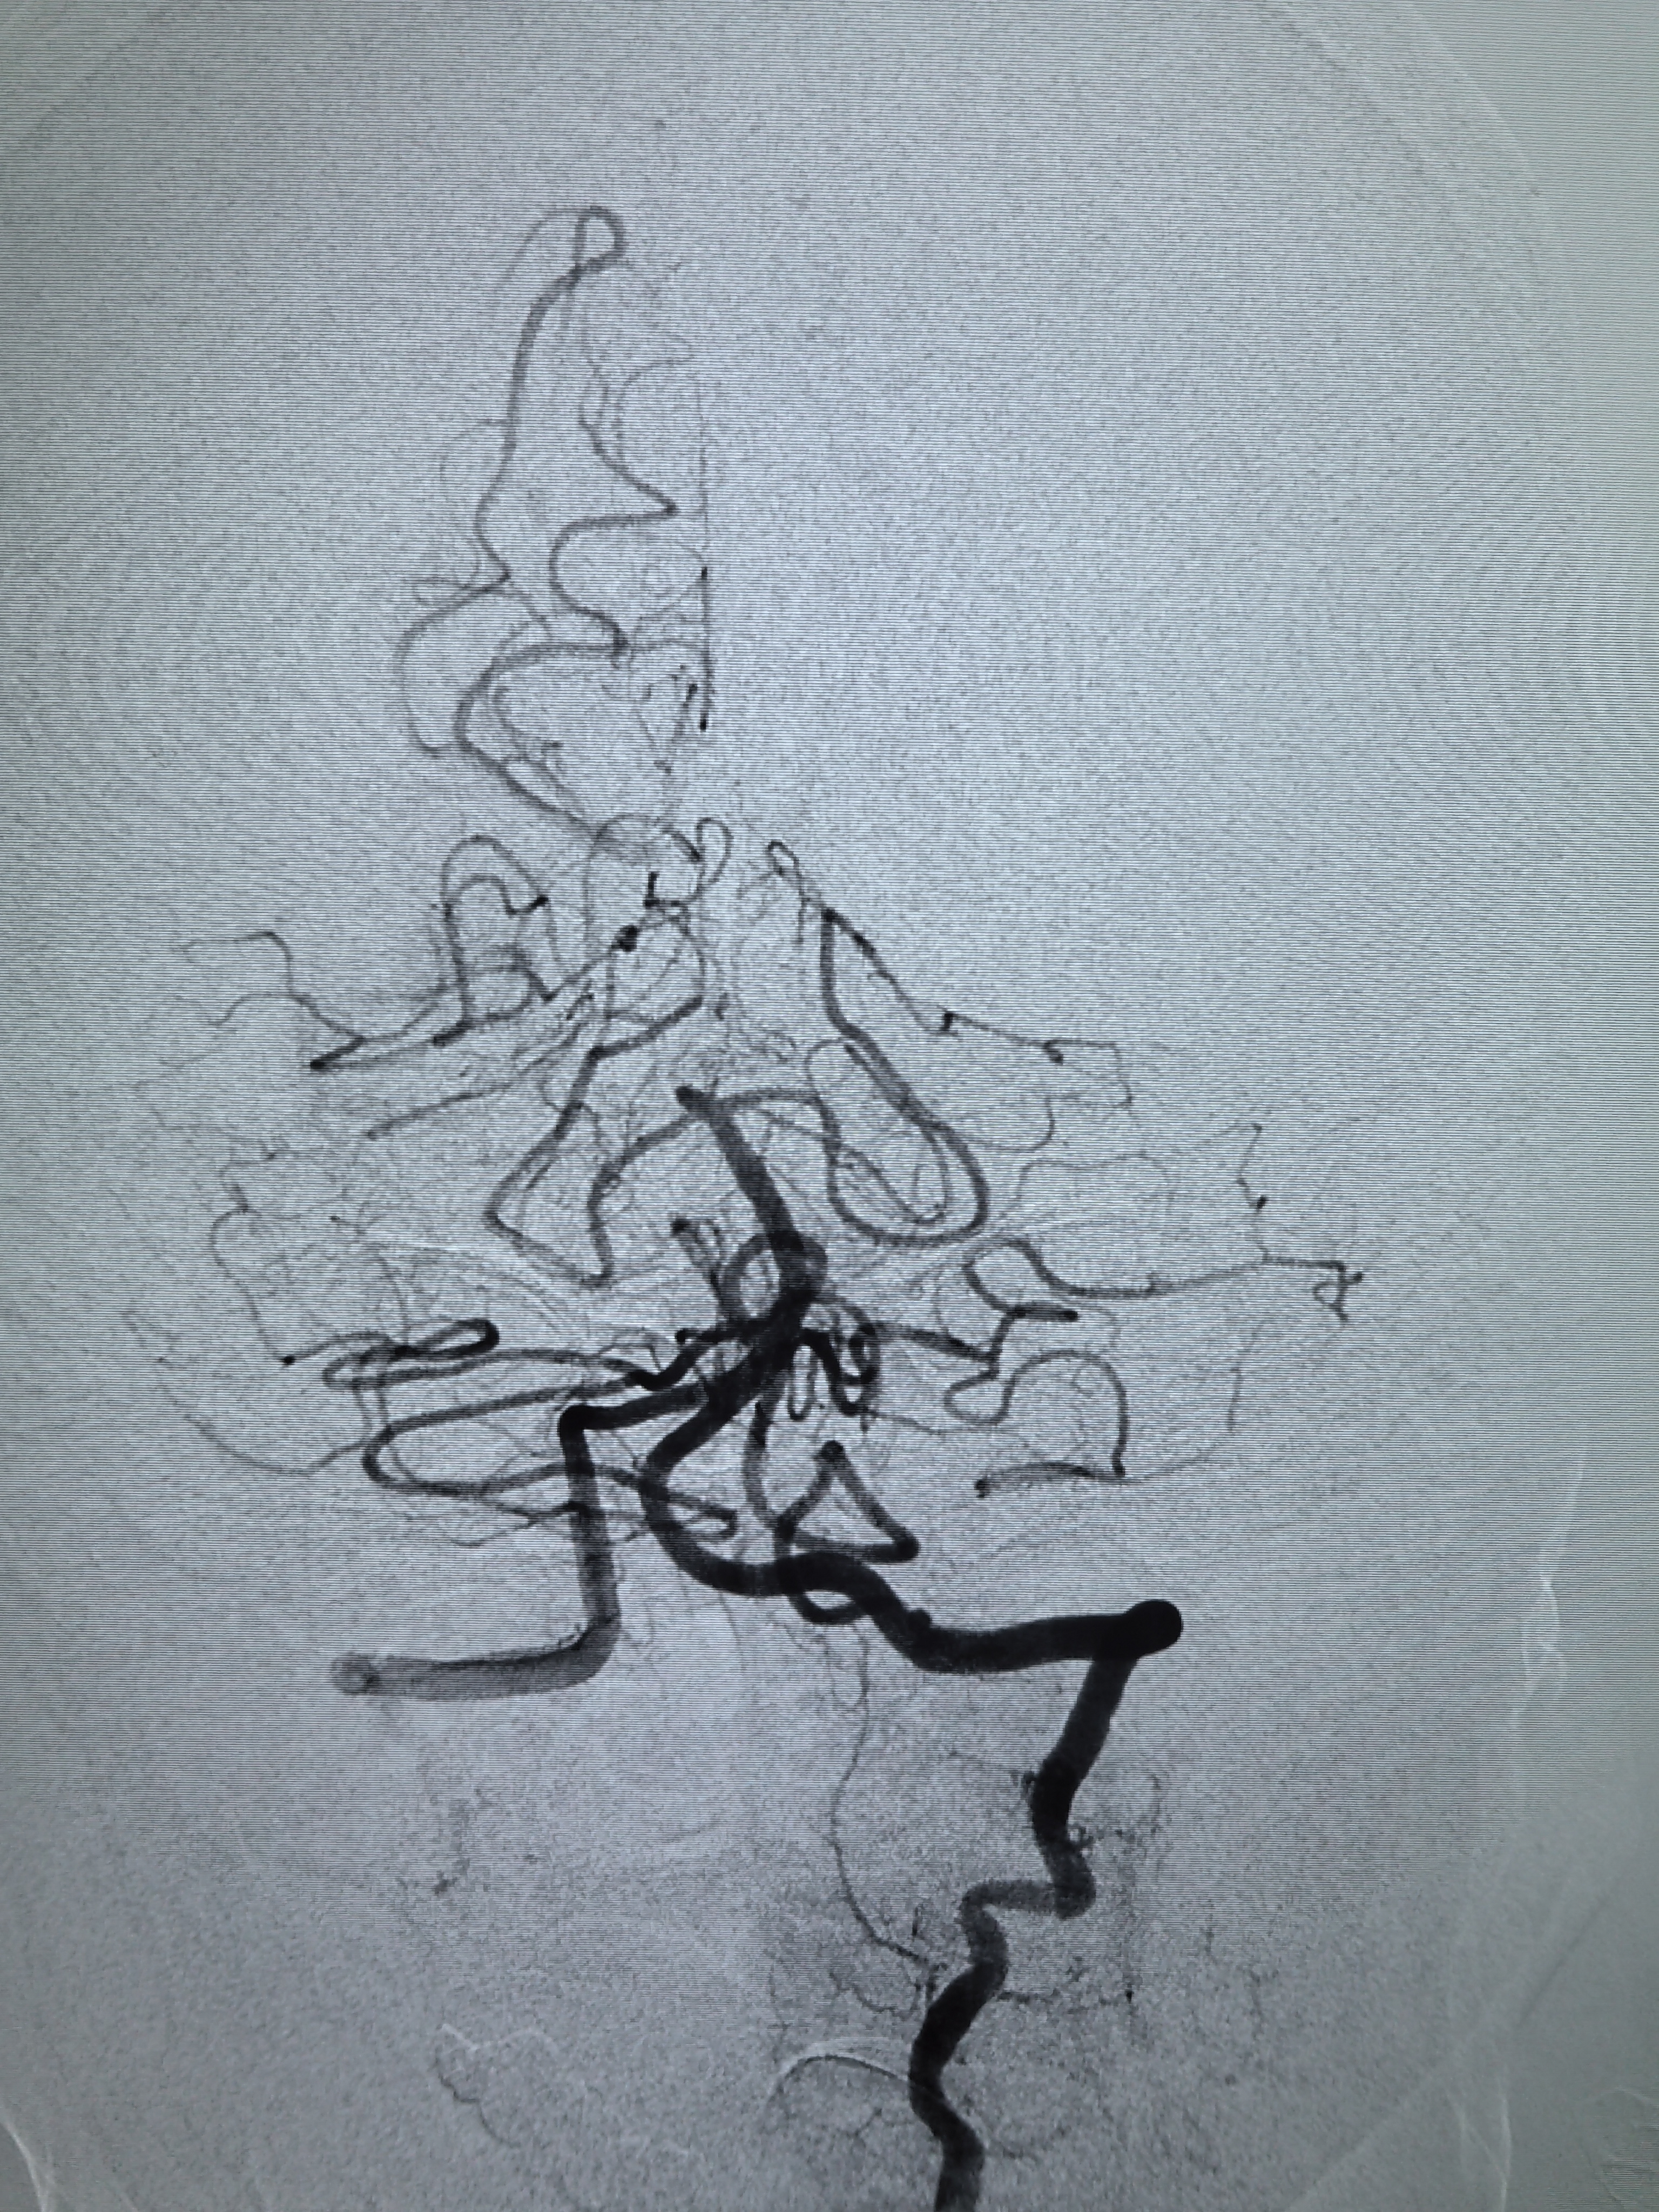

左侧颈内动脉造影!

左侧颈内动脉侧位造影!